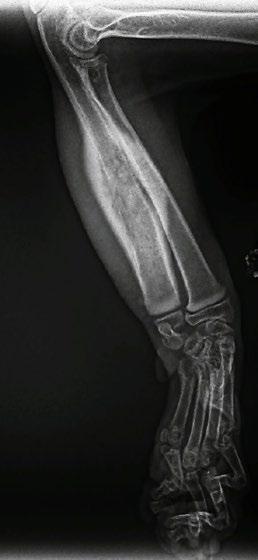

Four weeks later, Hotch was presented with marked lameness and a firm marked swelling of his left antebrachium. There were no obvious wounds or scabs, although he was hyperthermic. He was admitted for radiographs (see images) under sedation (dexmedetomidine 5µg/kg, methadone 0.3 mg/kg).

1

Radiographs showed signs of acute suppurative osteomyelitis, likely bacterial. This has a characteristic appearance in kittens, as the periosteum is not so strongly attached to the bone cortex, and the neutrophilic exudate lifts the periosteum, which then makes a florid new bone response ( blue arrow). Usually, these infections arise after a bite wound. The periosteal new bone formation is florid. Patchy portions of cortical bone lysis (yellow arrow) are also evident towards the centre of the lesion. At this stage we contacted Dr Richard Malik at the CVE as I had never seen anything like this before. Richard was also concerned about mild nutritional secondary hyperparathyroidism (NSH) due to the bone cortices appearing pale (osteopaenic), with an area of increased relative radiodensity immediately next to the growth plates (orange arrow). In NSH, the only normal bone is that laid down by endochondral ossification at the growth plates (and in this case—where new bone is laid down to wall off the infected bone), the rest of the skeleton is being broken down by osteoclasts under the direction of PTH.

Figure 1. Radiographs of the affected limb at presentation